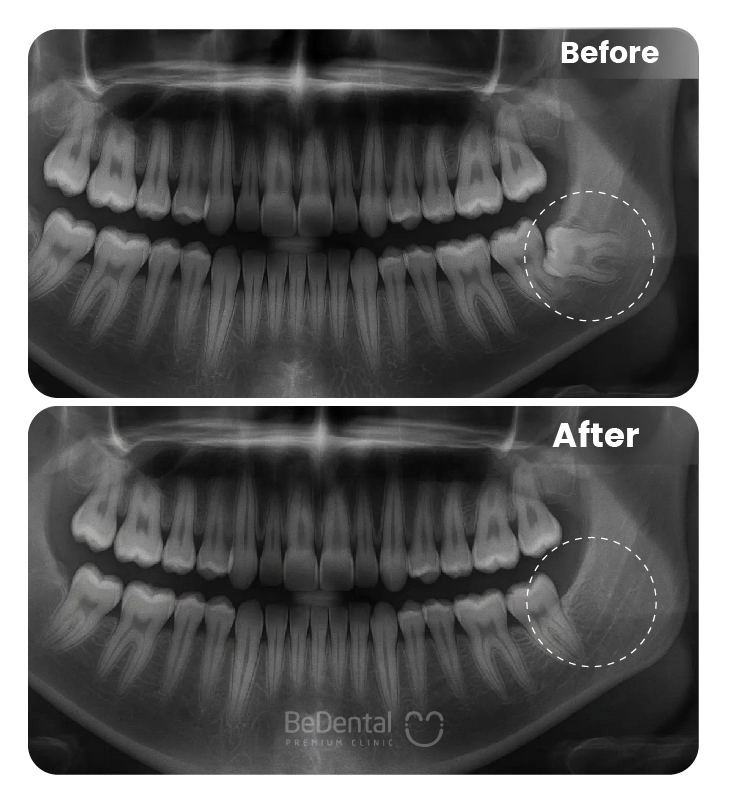

Trám răng rồi có niềng được không? Chỗ trám của răng có bị xước hay vỡ không? Đó là những nỗi băn khoăn của những bạn đã đi trám răng và hiện có mong muốn niềng răng thẩm mỹ. Thực tế theo các chuyên gia thì trường hợp trám răng xong chỉ cần đáp ứng các yếu tố dưới đây đều có thể niềng răng:

Trong nhiều trường hợp, nếu có điều kiện thì có thể áp dụng phương pháp niềng răng không cần đến mắc cài. Đây là phương pháp tối ưu nhất để niềng răng cho trường hợp răng đã trám. Như đã nói ở trên, trám răng rồi có niềng được không? Câu trả lời là có và sử dụng khay niềng Invisalign. Khay niềng này có ưu điểm là có thể tháo ra vào lắp vào nên không sợ những vết xước từ mắc cài đồng thời cũng rất dễ khi vệ sinh răng.